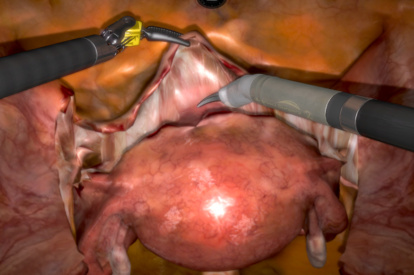

- Highly realistic graphics of human anatomy and simulation of tissue response to instruments

- Complication management: simulation of errors and bleedings

Hysterectomy Procedural Tasks Module

Hysterectomy Procedure Module

Vaginal Cuff Closure Module

Robotic Prostatectomy Module